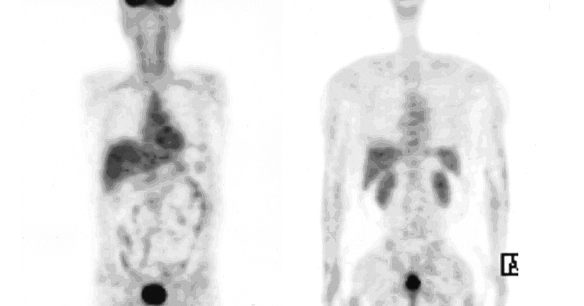

Figure 6

Follow-up examination with PET after 20 months showed that the hypermetabolic lesions of the head, neck and chest disappeared; however, the hypermetabolic lesion of the rectum showed no significant interval change.